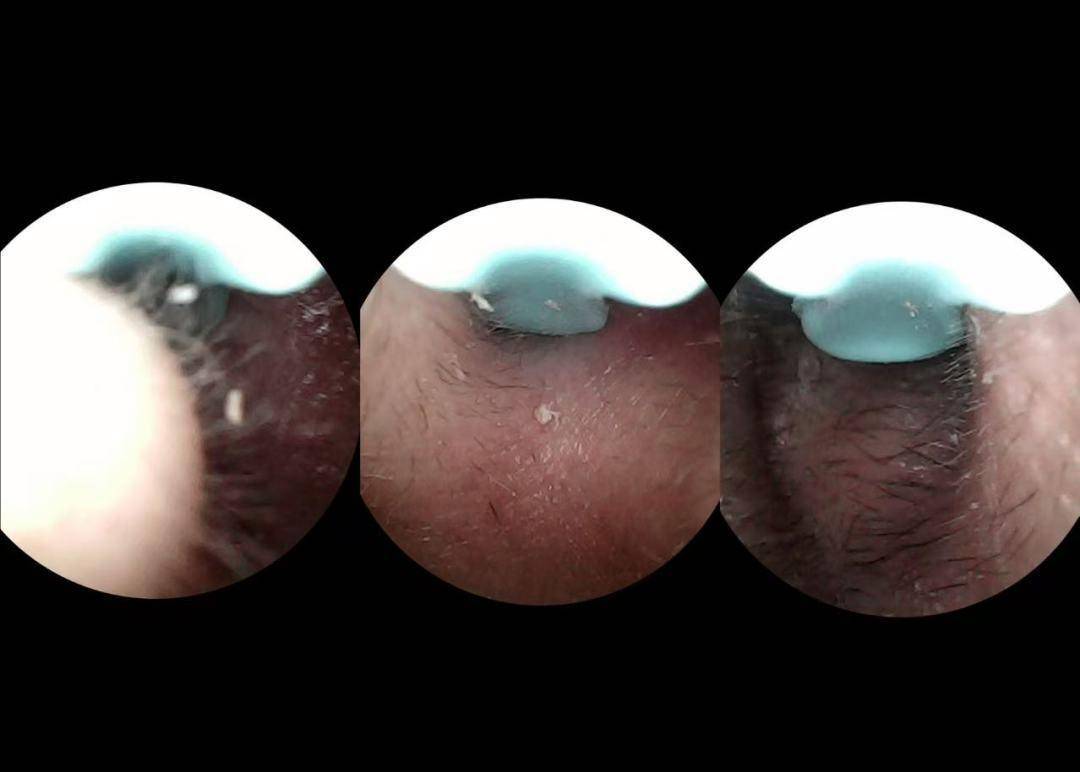

它搭载500万像素镜头,日常观察耳道轮廓和清理耳垢足够,但放大或查看深处细节时略显一般。环形LED补光灯亮度柔和,可照亮大部分耳道区域,深处光线稍弱。Wi-Fi连接顺畅,APP功能丰富,可以实时查看、拍照录像、调节光线,续航稳定。

摄像头像素为800万,画面清晰度够用,可以看到耳道主要区域,深处细节表现稍弱,需要多调整角度。内置LED补光灯亮度适中,光线均匀,个别角度可能有轻微暗角。整体操作简单,上手容易,续航约70分钟,适合日常家庭使用或新手,如果追求超高画质,这款可能略显不足。

镜头为500万像素,画质够用,可清晰看到耳道轮廓,但深层细节稍模糊,需要多角度调整。内置LED光源亮度足够,覆盖耳道大部分区域。Wi-Fi直连流畅,APP操作简单,支持实时预览、拍照和录像。整体表现适合日常清洁或偶尔使用,追求深度清理的用户可能觉得略有局限。